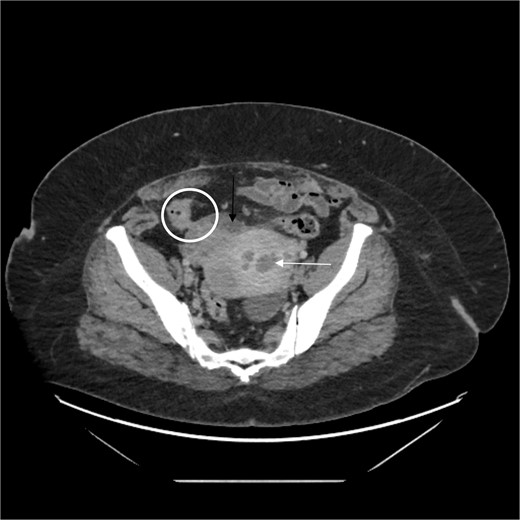

A complete blood count was normal. CT imaging demonstrated fluid and air in the uterus, associated with a phlegmon that communicated with the sigmoid colon (Fig. 1). An ovarian cyst was incidentally noted posterior to the uterus.

White arrow shows fluid in the uterus, black arrow shows phlegmon, and circle demonstrates colon and fistula.